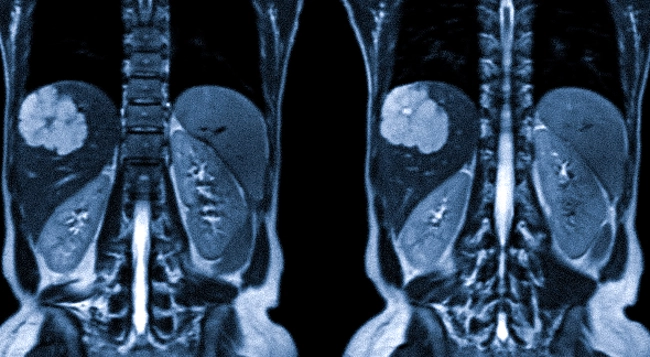

Скажу сразу. У меня обнаружили рак.

2. Боль в пояснице, к которой привыкаешь

Она была не острой.

Скорее фоном: потянуло, поныло, прошло.

Когда боль становится привычной — это не значит, что она нормальная.